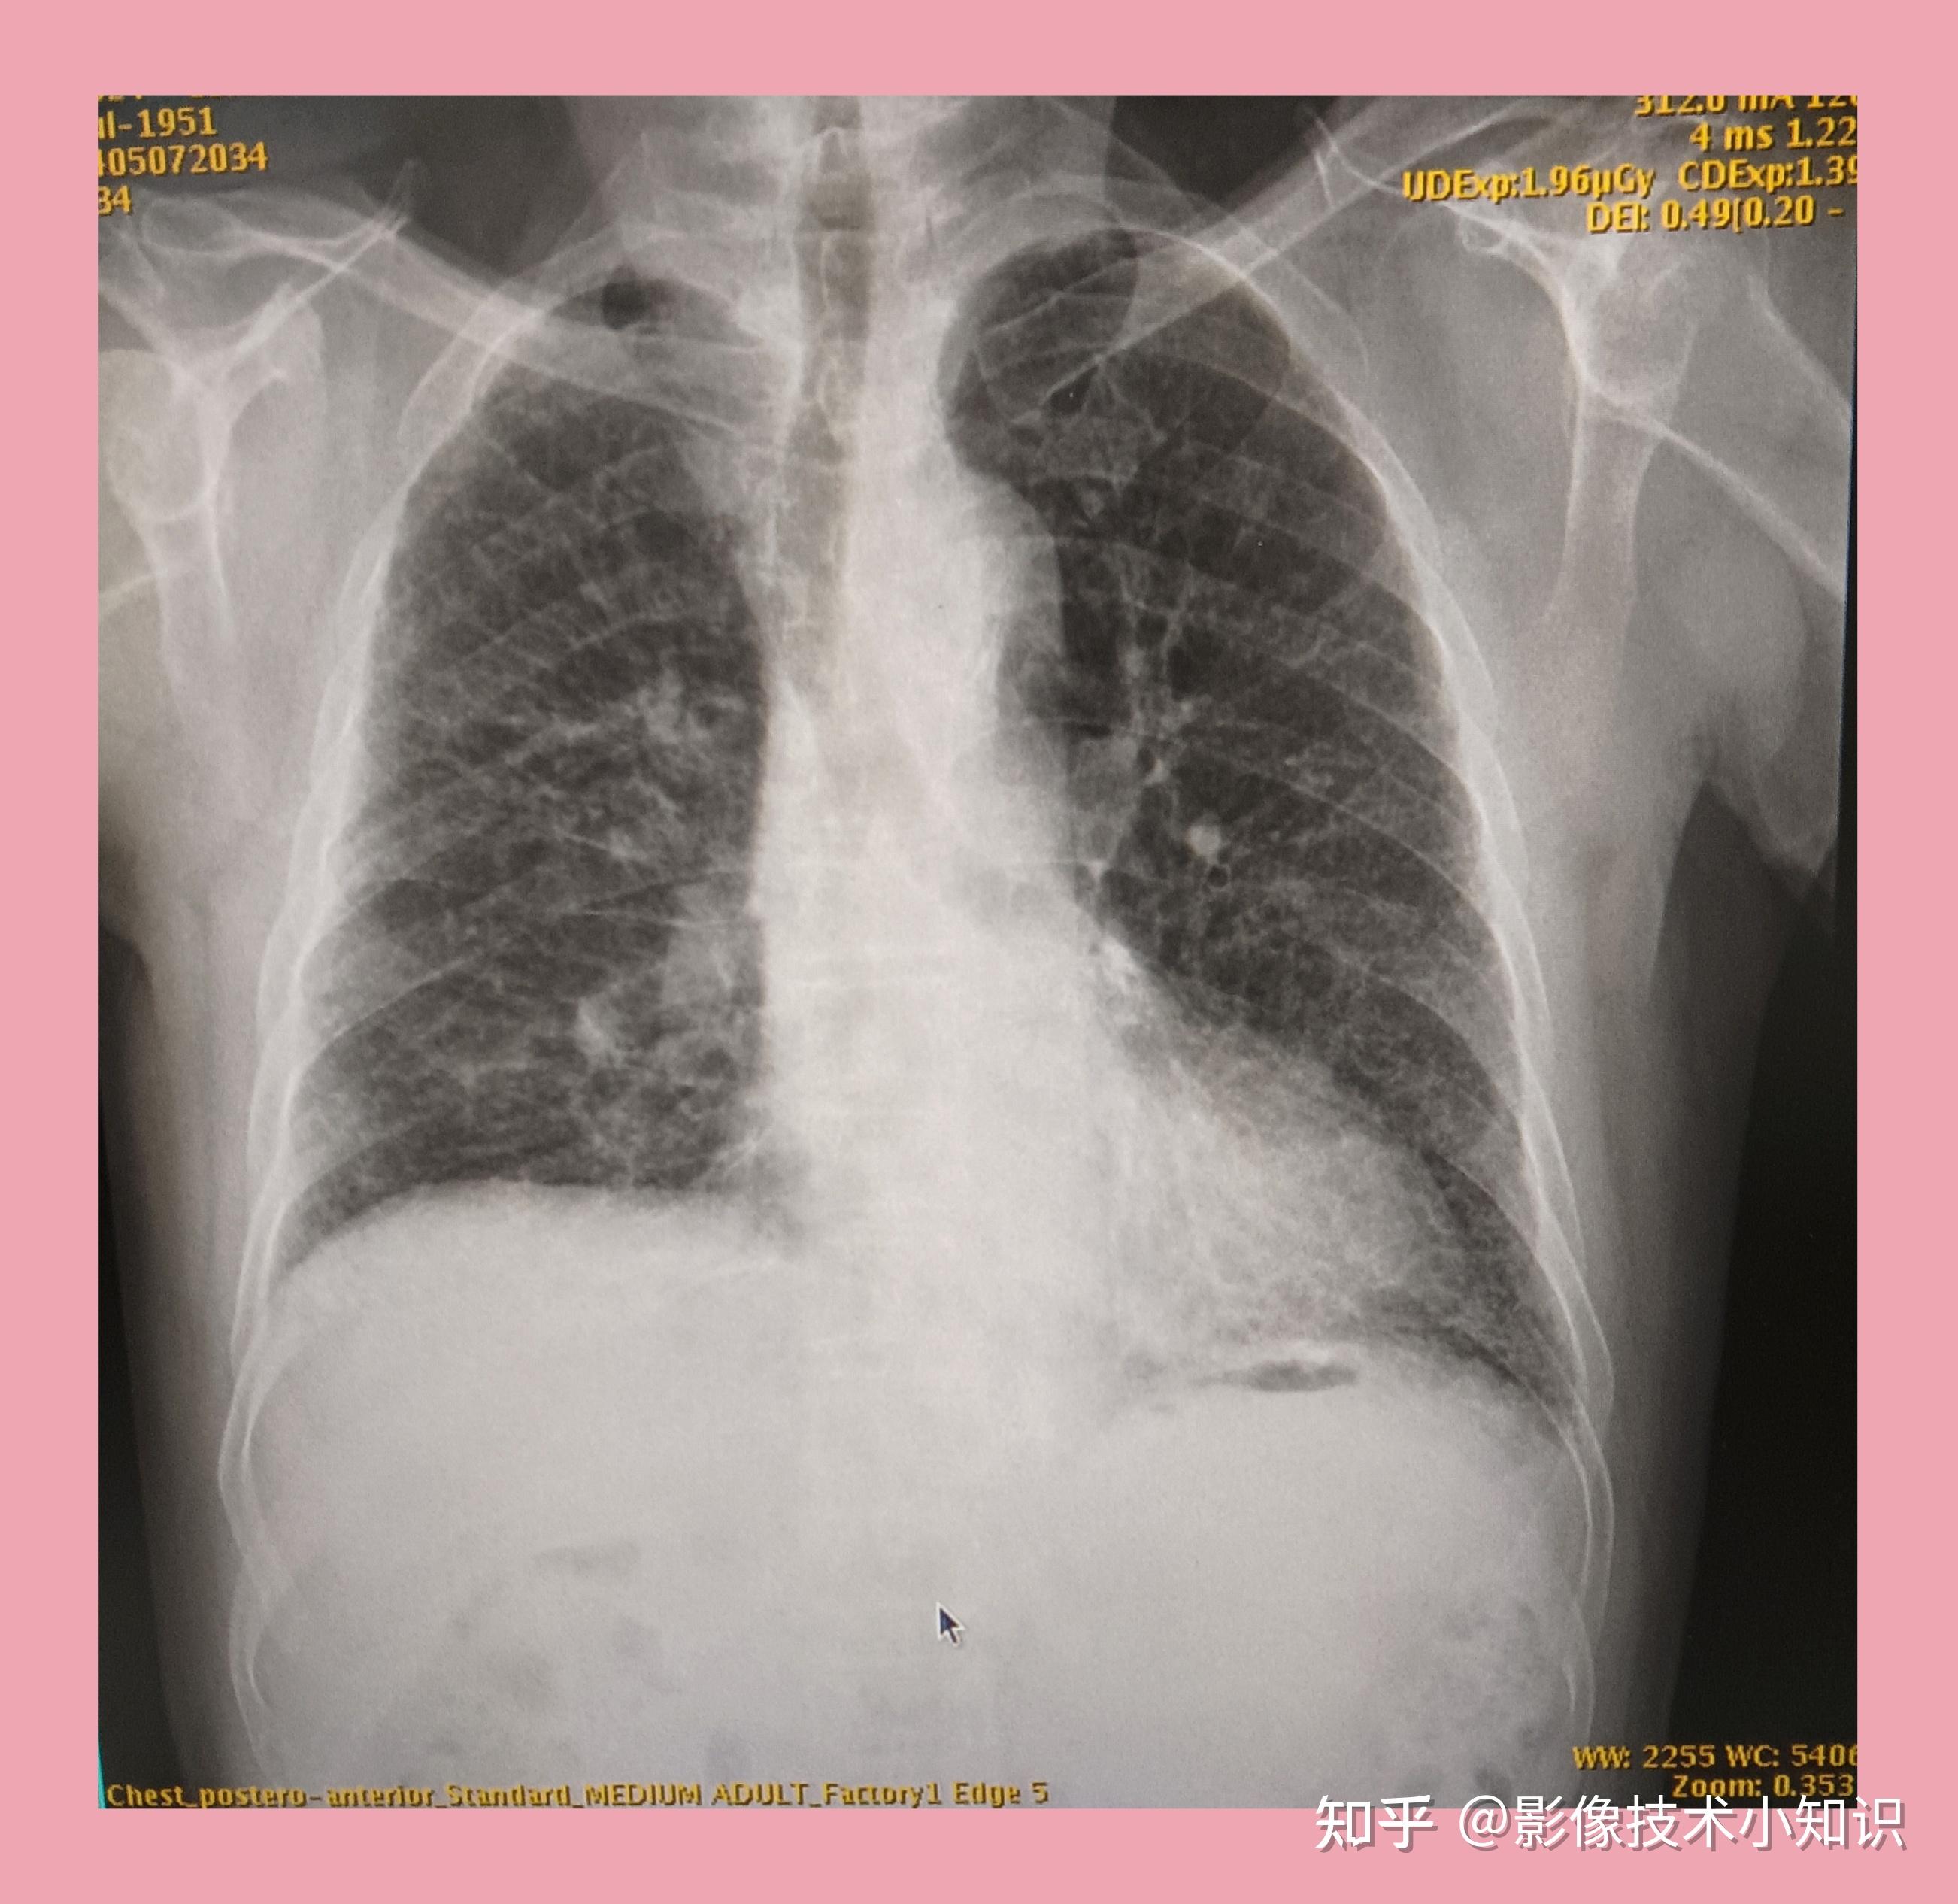

上图所示:右肺纹理增多,紊乱.右肺尖和中叶外野可以到钙化灶.

图9 双肺纹理增粗,增多,双上野明显,心影增大,注意心功能不全4.